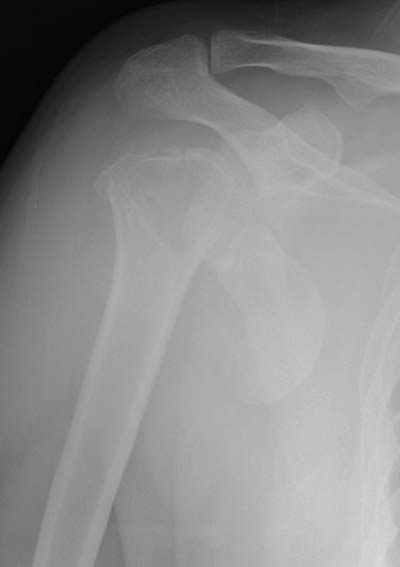

Пока я пользуюсь методикой принятой у нас (методика Сиэтла), также перкутанный спицевой метод, только сцицы 2.8 мм с резбой на конце.

Здесь случай перелома-вывиха плеча, больному 56 лет, после "дважды" закрытой неудачной репозиции, опять же ургентно взяли в операционную, после полного общего обезболивания попытались сделать репозицию, и фиксацию провели спицами.

Больной находился в повязке, примерно напоминяющей косыночную, рекомендованы движения в локтевом суставе и маятниковые движения в плече, спицы удалены в три недели (были случаи миграции)

Больной амбулаторный, предупрежден на случай осложнения АВН головки.